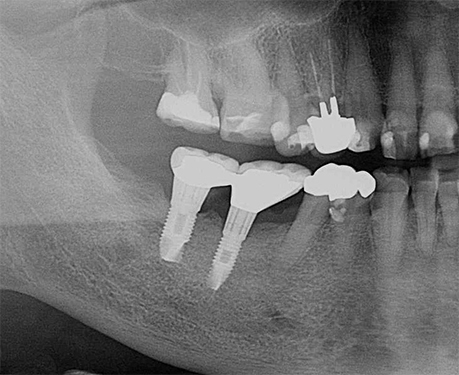

レントゲンでみたグラグラのブリッジと抜歯後の比較

インプラント埋入前の口腔内

インプラント埋入後の口腔内

治療期間3ヶ月

右下のブリッジを支える歯が重度歯周炎と歯根破折によりグラグラになり、抜歯後デンタルインプラントで治療しました。

Bさんの場合大きくかかる料金は、

手術料 フィックスチャー埋入術ZIMMER Spline TwistTM 200,000円

(210,000円税込み)

アバットメント料金 既製バットメント 45,000円

(49,500円税込み)

クラウン料金 メタルバッキング

ハイブリッドクラウン

75,000円

(82,500円税込み)

合計 320,000円

(352,000円税込み)

(一本分)